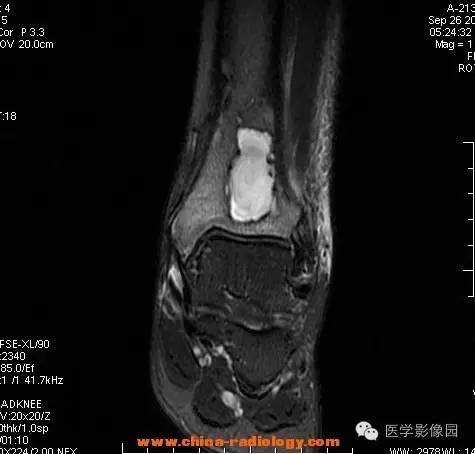

【病例】胫骨骨脓肿1例MR影像表现

影像学表现:胫骨中下段干骺端不未规则形长T1长T2信号,T2WI见不完整环形稍低信号影,T2脂肪抑制低信号更明显,并见胫骨下段及踝关节后外侧软组织呈弥漫稍高信号,增强明显不均匀强化,增强见低信号环内有环形强化影。

影像学表现:表现为长骨干骺端有椭圆形密度减低区,边缘有清晰的骨质硬化,病变与邻近正常骨髓腔境界清楚。MRI上T1WI呈低信号,少数呈等信号,T2WI多为混杂高信号,增强扫描可见环状强化,强化的脓肿壁薄而均匀。